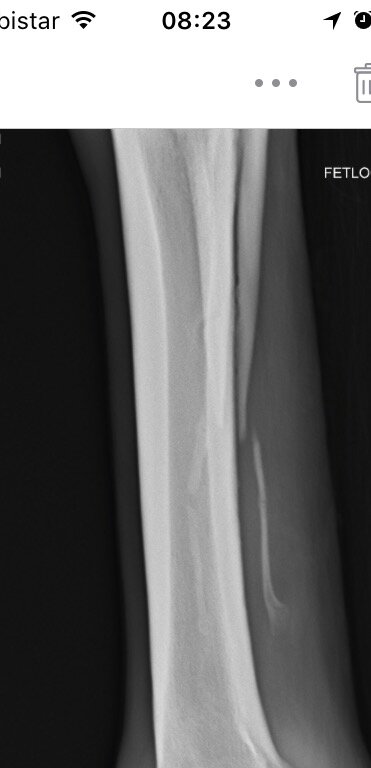

Ibbel schreef:Ik kan me niet voorstellen wat er mis zou kunnen gaan of wat de contra-indicaties van een operatie aan het griffelbeentje zouden kunnen zijn. Gebroken griffelbeentjes genezen niet, het afgebroken deel zal na verloop van tijd wel ingekapseld worden, maar dan heb je een los botfragment onderhuids zitten wat op allerlei structuren kan gaan drukken.

Cowgirl schreef:Ik zou die foto's opsturen naar een goede paardenkliniek en hun een oordeel laten maken.

Het ziet er behoorlijk heftig uit alhoewel ik ooit eens foto's gezien heb van en paard waarbij het gewoon verbrijzeld was..Daar konden ze niks mee, paard zou blijvende schade houden. Dier is dan ook ingeslapen.